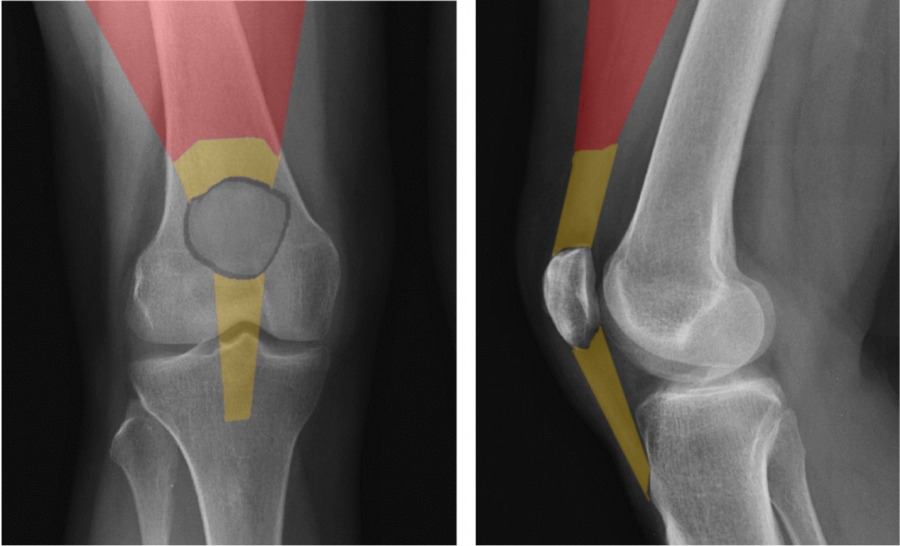

The Quadriceps mechanism includes a complex arrangement of muscular, tendonous, bony, synovial (membranous) and bursal tissue. The quadricep`s muscle comprises the majority of surface area of the frontal thigh and distal anatomy includes the patella and associated ligaments and tendons. Synovial and bursal tissue surround all structures to provide “frictional protection” for adjacent tissue layers and/or nutrient supply for hypovascularized regions.

The patella is classified as a Sesamoid bone, meaning it is encased within a tendon. It`s purpose is to serve as a mechanical “pulley” for the quadriceps during it`s action of knee extension. It improves net force production by approximately 30%.

The patella is apically shaped and it`s undersurface, or articular surface, is coated with thick hyaline cartilage to reduce friction as it glides over the distal femoral condyles, also coated with cartilage. When you disarticulate a chicken leg, the white “shiny” surfaces of that joint complex is articular cartilage.

The “retro patellar” (under) surface has a central prominence or ridge, designed to “track” within the central groove created by the two femoral condyles (6 and 7). The patellar under surface is also divided into 4 articular “facets” (medial 4, lateral 3, central, odd 2). Each facet has a range of motion dictated role in absorbing compressive loads as it operates as a pulley. The lateral facet absorbs load in extension of the knee, and correspondingly the medial and odd facets during flexion.  Compressive loads between the femur and patella can be enormous, often hundreds of pounds (Cohen et al, Amer J Sports Med, 29 (4), 2001 and Powers et al, J Ortho Sports Phys Ther, 44, 2014).  To accommodate these loads, the “retro-patellar” articular cartilage is the thickest in the body, approaching 7mm along the central ridge (Ahmed et al, J Orthop Res, 1987). Despite the durability of the patella, surface lesions do occur and unfortunately the hypo- vascular nature of articular cartilage restricts healing once damaged.

Surrounding patellar ligament complexes including the Medial Patella Femoral Ligament (MPFL) medially and the Lateral Patellar Retinaculum help guide centralized patellar movement. They also provide stability against “dislocating” forces.